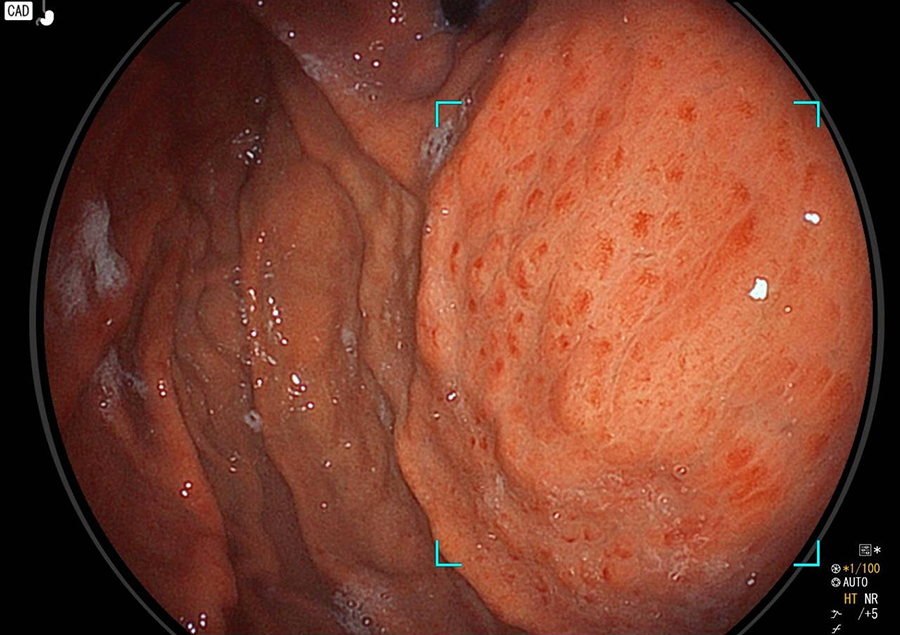

胃カメラ検査では、口又は鼻から内視鏡を挿入し、食道・胃・十二指腸の一部を観察します。直接胃や食道の粘膜を観察することができるので、色調や微妙な凹凸の変化が分かり、潰瘍・炎症・ポリープ・腫瘍などの診断が可能です。

胃カメラでわかる病気/病変

- 胃粘膜下腫瘍